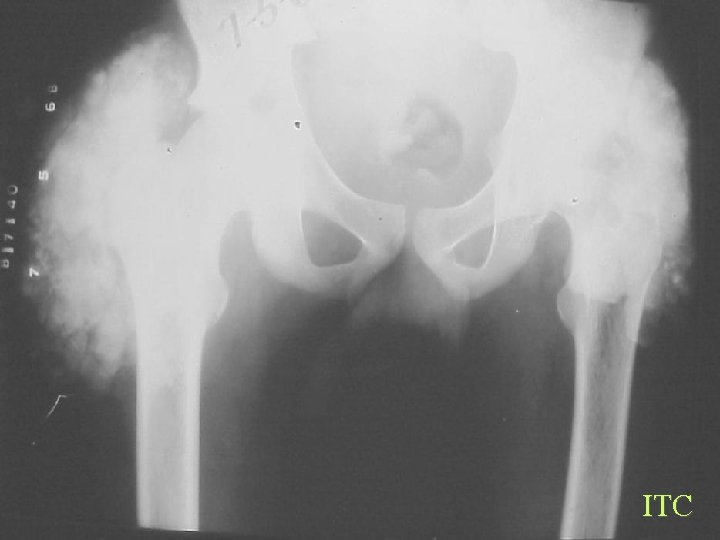

Soft Tissue Calcification By Cause Generalized Calcinosis Idiopathic Tumoral Calcinosis • • 10 -30 Yrs, black Elevated phosphate Single or multiple firm tumour like painless Hips, Shoulders, Elbows, Ankles Dense, Flocculent, Amorphous, 1 -20 cm, fluid levels Dx of exclusion

ITC